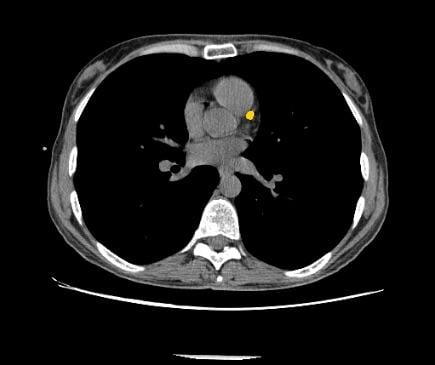

β1600 Q.Clear Digital Reconstruction of [68Ga]Ga, Zebra Medical Vision Announces FDA 510(k) Clearance of,